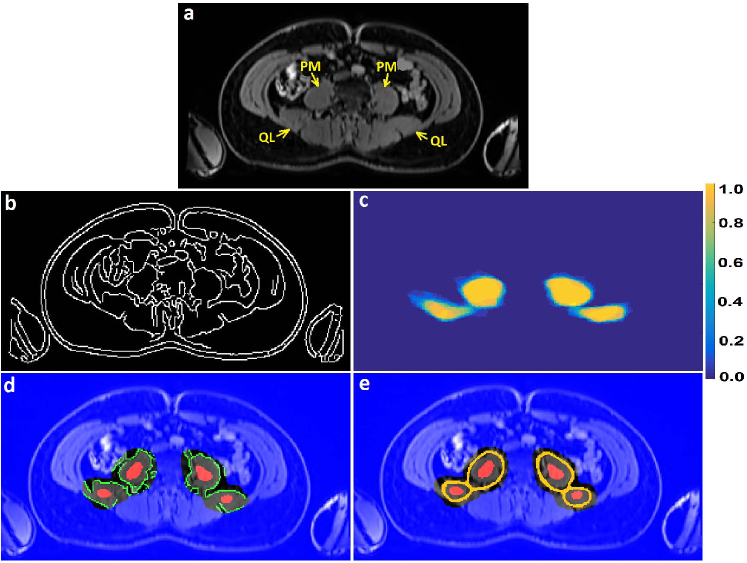

The classification priors of the samples could be estimated by any method such as the multiatlas registration or the hierarchical random forest classifier proposed in [Fallah 2018a, Fallah 2018b, Fallah 2019b, Fallah 2019a]. This happened when the classification probabilities estimated by those methods were not accurate enough to be considered as final classification probabilities (posteriors) rather as initial classification probabilities (priors). For example, the classification probabilities estimated by the proposed forest could not differentiate different kinds of cardiac adipose tissues on fat-water MR images. They could only differentiate the overall adipose tissues from nonadipose tissues. This was due to lack of spatial information in the forest, similar contrasts and features of the cardiac adipose tissues, and weak boundaries between them. The cardiac adipose tissues were spatially close to each other and separated only through thin septa which were hardly detectable under spatial resolution of standard clinical scanners at 3 T. Figure 1 shows voxelwise classification probabilities estimated by the proposed forest for the cardiac adipose tissues and the resulting segmentations on various slices of a fat image. Figure 2 shows overall segmentations of the cardiac adipose tissues based on the voxelwise classification probabilities estimated by the proposed forest on some axial slices of a fat image. Despite inaccuracies of the priors, they, features, and the spatial (neighborhood) relationships of the samples could pave the way for another classifier such as the neighborhood graph to classify the samples more accurately. For example, the priors could approximately localize an addressed object in an image and thereby speed up or reduce the complexity of its accurate segmentation. The more accurate classification probabilities were called the posteriors. Accordingly, the neighborhood graph was supposed to estimate the classification posteriors of every sample (vertex) with regard to its features, its priors, and its spatial (neighborhood) relationships with other samples of the same resolution .

Figure 6 shows these subsets on an axial slice of a water image with the important (foreground) class being the spatial regions of the psoas major and quadratus lumborum muscles.

The graphs proposed in section 3 and section 4 tried to implicitly or explicitly detect boundaries between different classes (e.g. objects) in spatial domain (e.g. image). The implicit boundary detection used the Tukey’s function of the features differences of the connected samples and the explicit boundary detection applied a 3D Sobel operator to each intensity channel of the samples. Both of these techniques could enhance the accuracies of a classification in spatial domain. However, their performance was limited when the features of different classes were similar or the boundaries were too weak to be detected. An example of these cases was segmentation of cardiac adipose tissues on fat-water MR images. As shown in Figure 1 and Figure 2 the random forest classifier proposed in [Fallah 2018a, Fallah 2018b, Fallah 2019b, Fallah 2019a] could only detect the overall adipose tissues but could not differentiate different kinds of it. The neighborhood graph proposed in section 3 or section 4 took the priors, the features, and the classification reliabilities of the samples and applied an implicit or explicit boundary detection. This could enhance the accuracy of the segmentation of the cardiac adipose tissues on fat-water MR images but the performance was still unsatisfactory. Figure 7 shows the voxelwise classification posteriors estimated for these adipose tissues by the implicit and/or explicit boundary detection on two axial slices of a fat image. To tackle features similarities and undetectable boundaries between different classes in spatial domain, we further extended the spatial feature-based subgraph by guiding the classification through additional information. These information got encoded into a diffusion-based susceptible-infected-recovered (SIR) model proposed in [Bampis 2017].